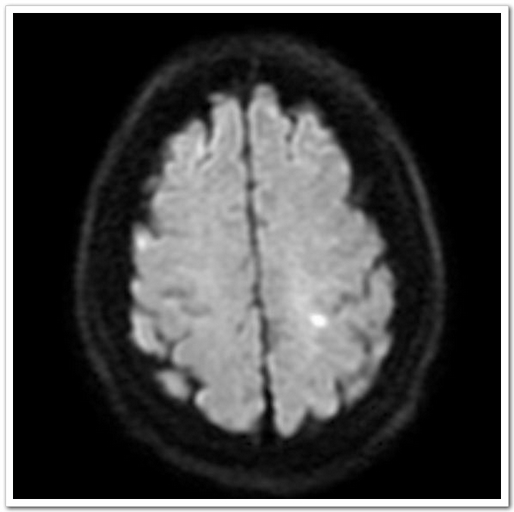

60岁的张阿姨这天正在家中看电视,突然感觉自己右侧上肢使不上劲,主要为右手拿不稳东西,日常生活动作突然不能像平时那样完成。真是人在家中坐,病从天上落,症状持续无明显缓解,也无进一步加重,遂至深圳大学总医院神经内科就诊。入院后头颅CT排除脑出血;颅脑磁共振平扫MRI+MRA:1.左侧顶叶皮层急性腔隙性梗死灶。2.双侧额、顶叶皮层下少许缺血灶。3.头颅MRA未见血管异常。

图1:MRI:左侧顶叶皮层急性腔隙性梗死灶